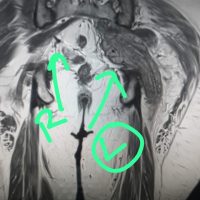

Magnetic resonance imaging was suggestive of features of non-union of talus fracture with secondary degenerative changes. Secondary arthritis changes involving the talocalcaneal joint, with associated synovial inflammation. Injury to the deltoid ligament with high-grade strain with partial thickness tear in the anterior and posterior talofibular ligaments and calcaneofibular ligaments (Fig. 3).

Figure 3: Pre-operative magnetic resonance imaging.